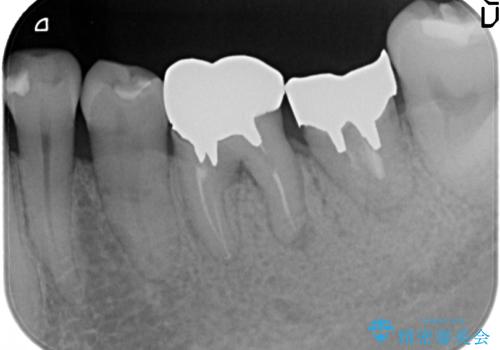

- 左下の銀歯が外れたので診て欲しいといらっしゃった方の症例です。

他院にて再装着したが不安なので、根管治療からやり直したいとのことでした。

再根管治療終了後、オールセラミッククラウンによる補綴を行いました。

今回用いたオールセラミッククラウンはジルコニアフレームという白い素材の上にセラミックを盛っているため、審美性が非常に高いのが特徴です。

また、ジルコニアは人工ダイヤモンドの材料にも使われているほど高い強度を持っており、そのためオールセラミッククラウンは審美性だけでなく、奥歯やブリッジの補綴も可能とするクラウンです。